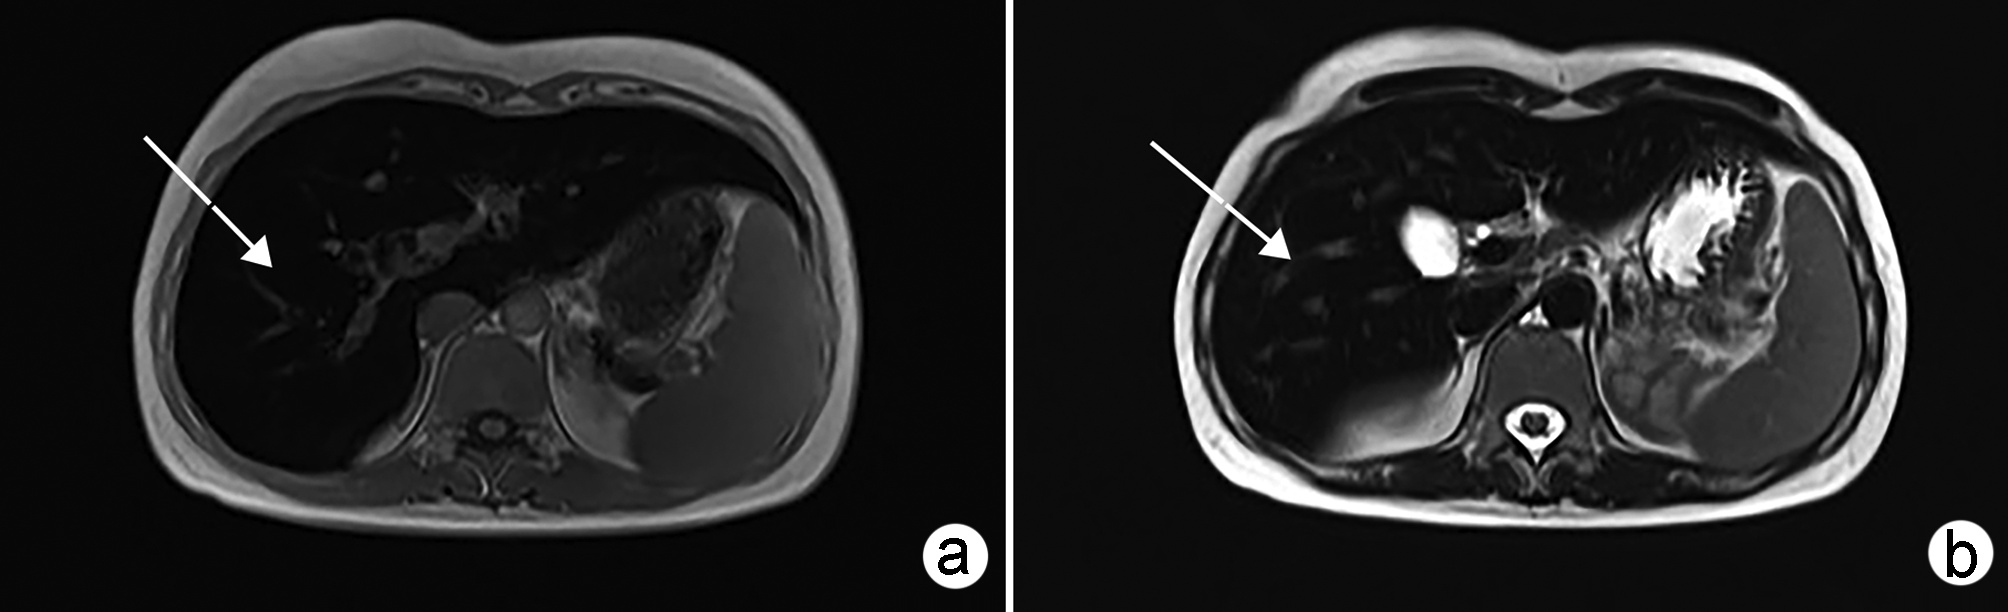

Application value of indocyanine green fluorescence imaging in laparoscopic cholecystectomy of difficult gallbladder

Abstract(1421) HTML (256) PDF (2744KB)(92)

Abstract:

Objective  To investigate the clinical utility of indocyanine green (ICG) fluorescence imaging in difficult laparoscopic cholecystectomy (LC).  Methods  The clinical data of LC patients from October 2021 to December 2021 in the First Affiliated Hospital of Anhui Medical University were retrospectively analyzed. Based on whether ICG fluorescence imaging was used and whether gallbladder difficulties were detected, the patients were divided into four groups: ICG common gallbladder (Group A), ICG difficult gallbladder (Group B), common gallbladder (Group C), and difficult gallbladder (Group D). The operative time, intraoperative bleeding, length of hospital stay, hospitalization cost and postoperative complications were compared. Comparison of normally distributed continuous data between groups was performed by t test. Comparison of categorical data between groups was performed using the chi-square test or Fisher's exact probability method.  Results  The operative time, intraoperative bleeding, length of hospital stay, hospitalization cost and intraoperative complications in group A were comparable to those in Group C (all P > 0.05). The operative time and intraoperative bleeding were (75.41±12.96) min and (18.27±6.97) mL in group B, vs (106.78±19.21) min and (23.99±8.43) mL in group D, respectively, and the differences were statistically significant (all P < 0.05), while the length of hospitalization, hospitalization cost and postoperative complications in group B were comparable to those in group D (all P > 0.05).  Conclusion  The benefits of ICG fluorescence imaging during LC in patients with the common gallbladder are not obvious. However, in difficult gallbladder cases, ICG fluorescence imaging can improve biliary tract exposure and reduce operation time and intraoperative bleeding.